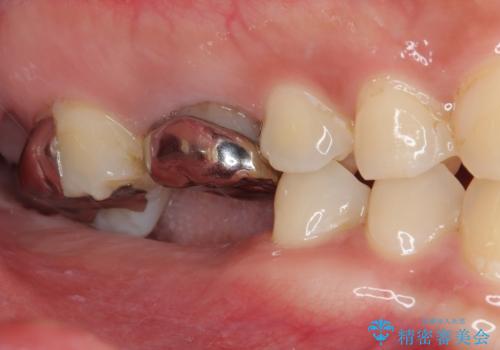

右側上下と左上の小臼歯が一本ずつ少なく、さらに骨格的な左右差もあり上下の真ん中の位置がずれています。

下顎のデコボコの解消と、真ん中の位置を改善するために左下の小臼歯を抜歯することとしました。